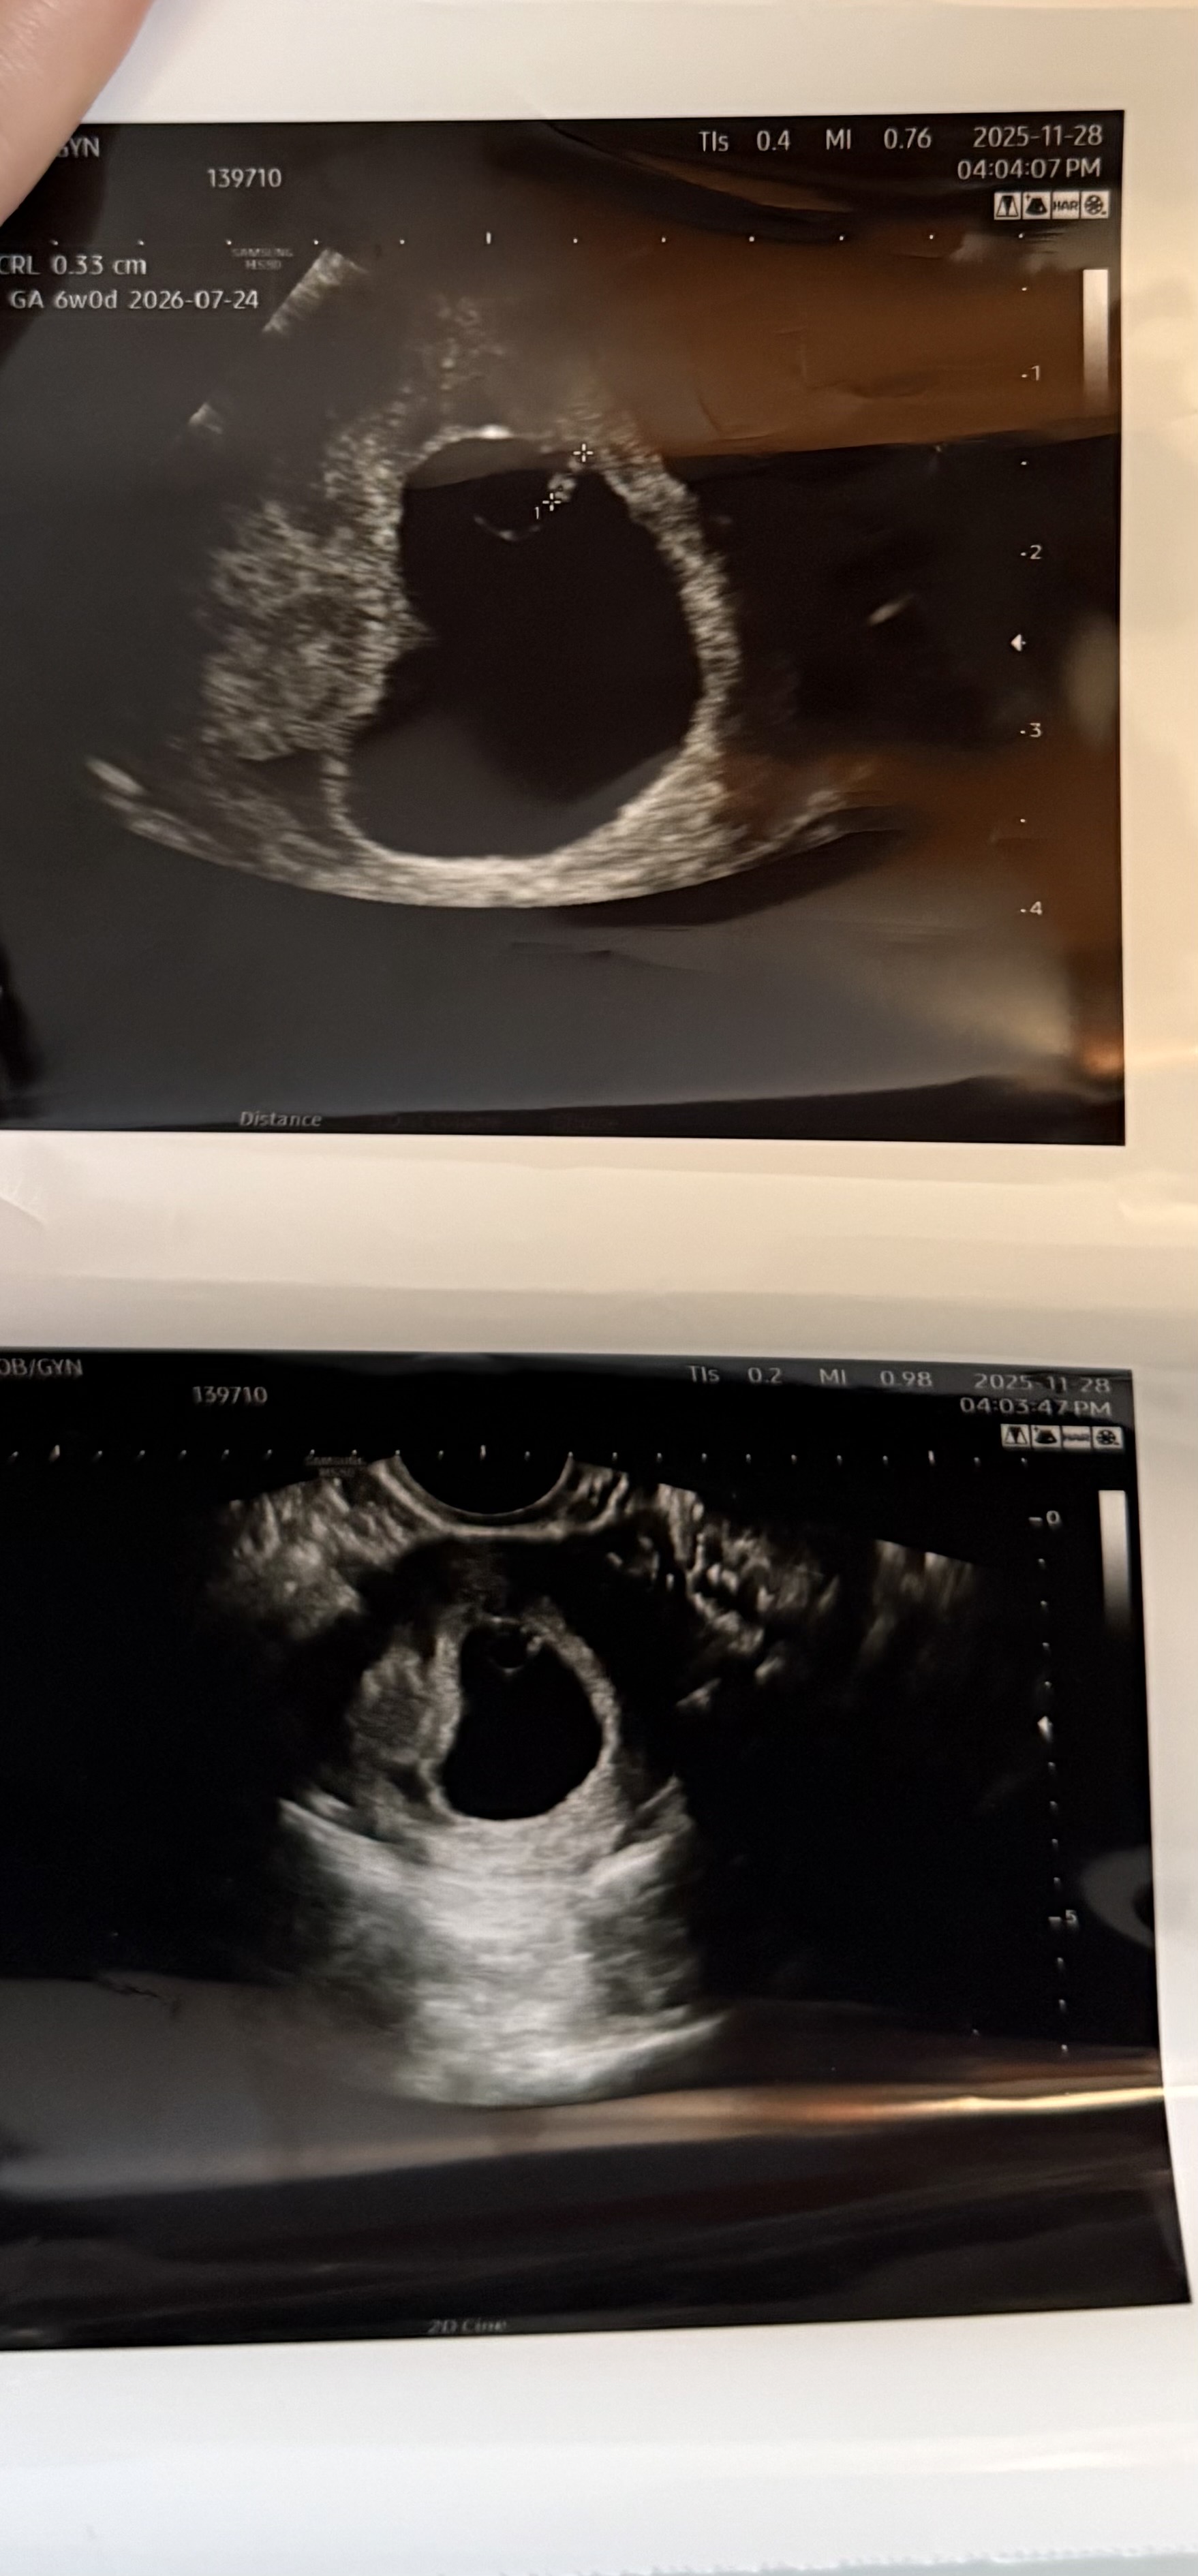

2주전에 아기집을 봤을때 크기가 5주정도 라고 말씀 주셨습니다 어제 가서 보니 아기집은 커졌는데 아기가 생기기만 하고 거의 안컸대요 근데 심장은 뛰고있어요 심장 소리는 못듣고 초음파 상으로 보기만 했습니다 다시 정상적으로 성장 할 확률이 거의 없다고 혹여 정상적으로 성장을 하더라도 문제가 있을수있다고 마음의 준비를 하고 월요일에 다시 보자고 하셨습니다 방법이 없을까요?